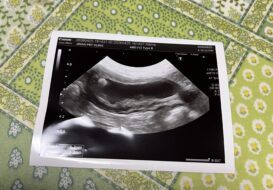

さつまいも🍠キューちゃんわんケア日記 89 🎥IMG_6260 狂犬病予防注射 フィラリア予防の検査 春の健康診断 血液検査 尿検査 超音波検査 尿検査 シュウ酸カルシウム結晶あり 膀胱結石 有り 要サプリメント 腎臓結 […]